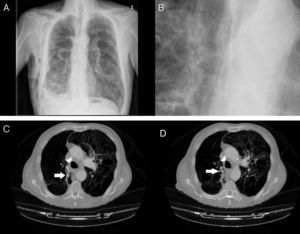

Hemos realizado 9 procedimientos en 8 pacientes con FAP. La serie se compuso de 7 hombres y una mujer, con una mediana de edad fue 68,5años. Todos los pacientes tenían comorbilidad asociada importante: enfisema pulmonar severo 7 pacientes, insuficiencia respiratoria 5, trombocitopenia inferior a 20.000 plaquetas uno y cardiopatía isquémica otro paciente. En 6 pacientes la FAP se produjo tras la aparición de un neumotórax espontáneo secundario a una enfermedad pulmonar de base (fig. 4A y B), en otro por un neumotórax iatrógeno y en el octavo tras la resección anatómica por un cáncer de pulmón.